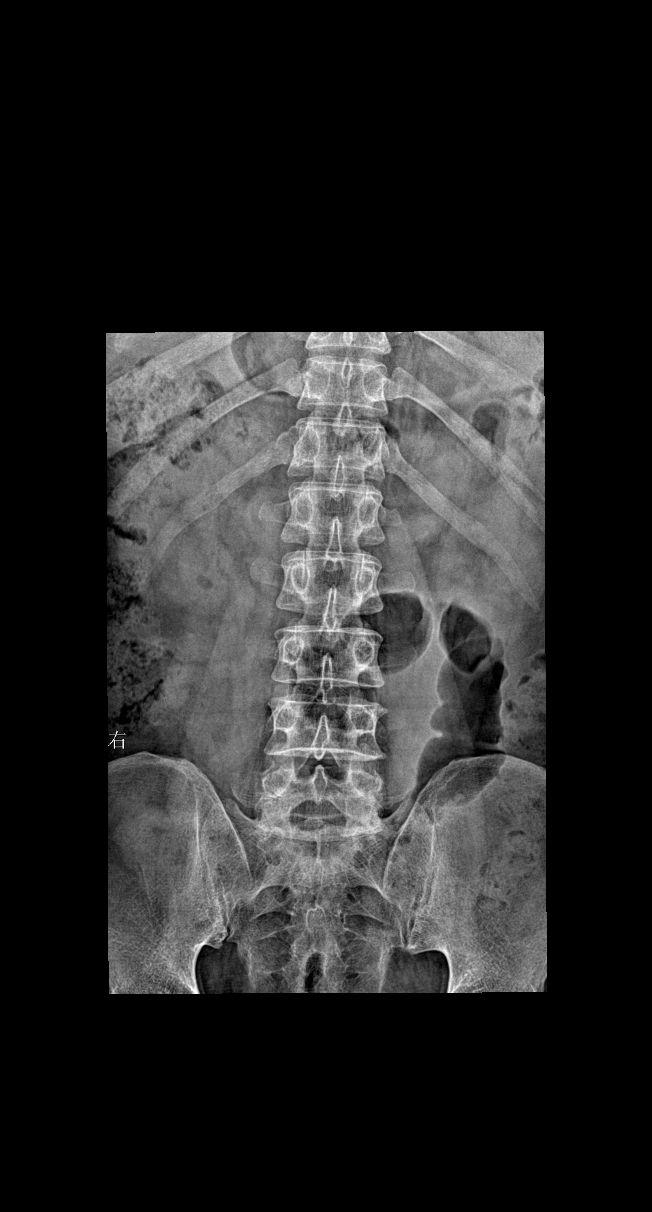

男34 腰椎疼痛 颈椎正侧+腰椎正侧